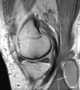

Idiopathic popliteal cyst